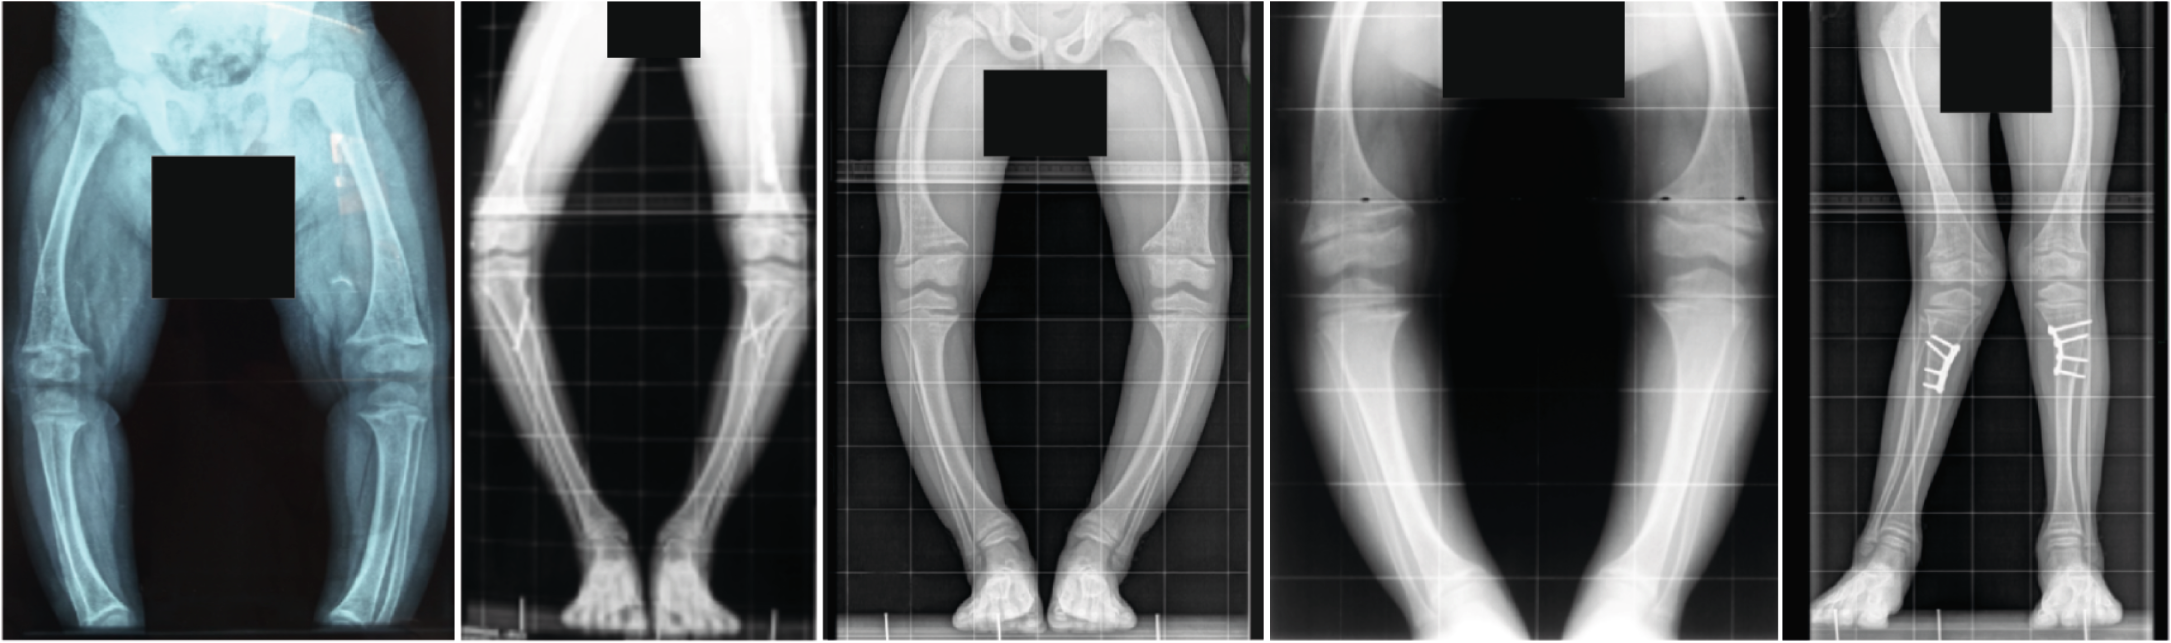

Fig. 1: Radiographs of the lower extremities of children with X-linked hypophosphataemia.

The patients show disproportionate short stature with genu varum (bowed legs) or genu valgum (knock-knees). The radiographs reveal severe leg bowing, partial fraying and irregularity of the distal femoral and proximal tibial growth plates. Note the lack of bone resorption features. Reprinted from ref. 17, CC BY 4.0.